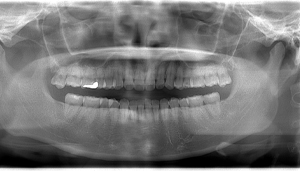

- Before

- After

CTで親知らずと神経(下歯槽管)の位置を確認しました。

親知らずと神経は一定の距離があり、麻痺などのリスクがほとんどないと判断できます。

口腔内

半埋伏の親知らずでした。3糸縫合しました。